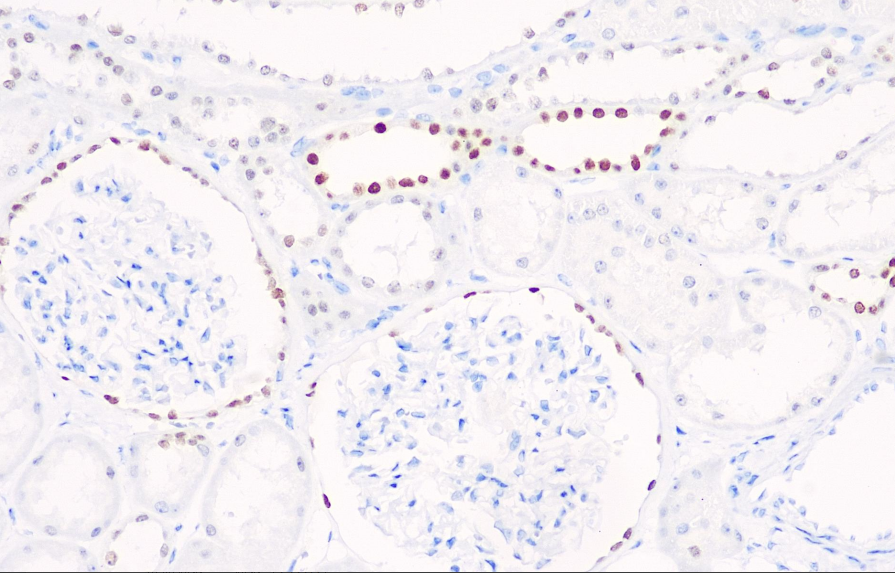

Positive control: kidney

PAX-2 is an allogeneic gene that is strongly expressed during renal development. After ureteral bud induction, the PAX-2 gene is expressed in the posterior renal stroma and is a key factor in the interstitial - epithelial transition. Animals lacking PAX-2 will present with severe renal malformations and cysts, but no solid tumors will occur. Mazal et al's research indicates that PAX2 is mainly expressed in clear cell renal cell carcinoma (88%), while its expression rate is low in papillary renal carcinoma and chromophobe renal cell carcinoma. Therefore, this antibody is helpful for the classification of renal tumors. PAX-2 can also be used in the research of liver metastatic clear cell renal cell carcinoma and primary clear cell renal cell carcinoma. Recent literature reports indicate that this antibody is used in the study of metastatic ovarian serous papillary carcinoma (Pax-2 positive) and primary breast cancer (Pax-2 negative).

The Pax-2 antibody reagent can specifically bind to the Pax-2 molecular antigen. The immunohistochemical kit containing the Pax-2 antibody reagent is suitable for the auxiliary diagnosis of liver metastatic clear cell renal cell carcinoma, primary liver clear cell carcinoma, metastatic ovarian serous papillary carcinoma and primary breast cancer.